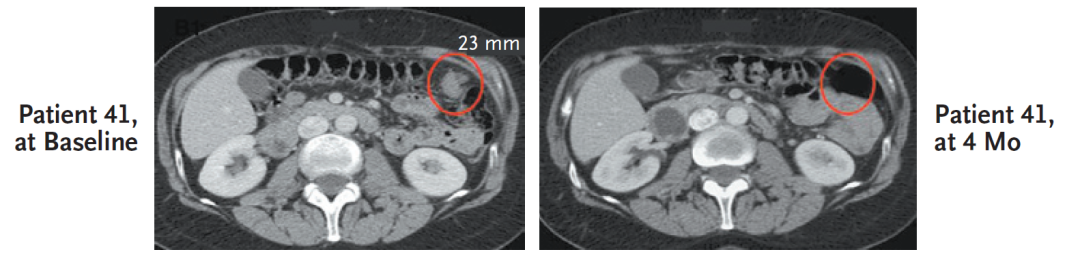

首位接受奥拉帕利治疗的卵巢癌患者(41号病人),该患者携带BRCA1突变,接受奥拉帕利治疗4个月后病灶完全消失,持续1年14